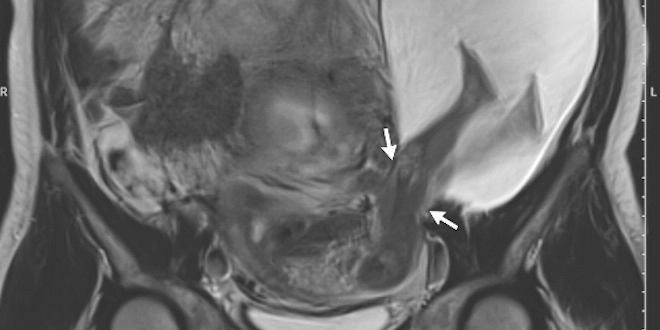

L'image, publiée le 22 décembre dans la revue médicale New England Journal of Medicine, a été remarquée et commentée par notre confrère Marc Gozlan sur son blog Réalités biomédicales : il s'agit de l'IRM du ventre d'une femme de 33 ans, dans sa 22e semaine de grossesse. Une anomalie saute rapidement aux yeux : les jambes du fœtus se situent hors de l’utérus, suite à une hernie (voir encadré) du sac amniotique au travers du muscle utérin - rompu sur 2,5 cm.

Dans les notes accompagnant le cliché, les auteurs notent que "la patiente et son partenaire ont été informés des risques potentiels de ces découvertes", notamment la rupture utérine complète, l'accrétion du placenta, une naissance prématurée, et la nécessité de recourir à une ablation de l'utérus (hystérectomie).

Ceux-ci ont opté pour une poursuite de la grossesse. À 30 semaines, une échographie a révélé que la rupture de la paroi utérine mesurait désormais cinq centimètres. La hernie incorporait désormais non seulement les jambes, mais également l'abdomen du fœtus. Une césarienne a été réalisée, actant la naissance, en septembre 2015, d’un bébé de 1,385 kg, en bonne santé.